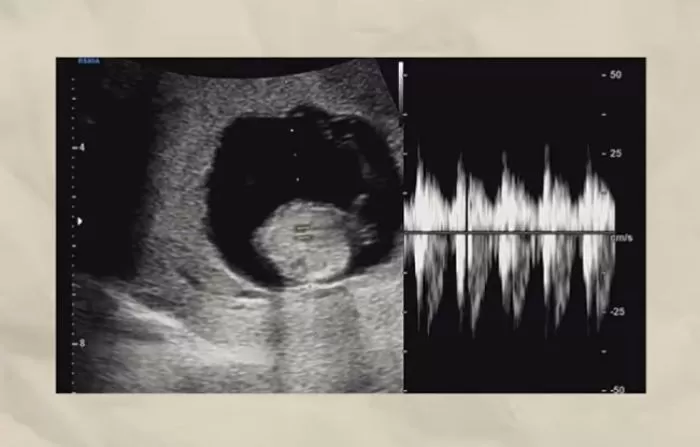

임신 소식 알린 윤승아·김무열 부부, 남편 김무열이 아내 윤승아의 배를 만지며 아이에게 말을 걸어